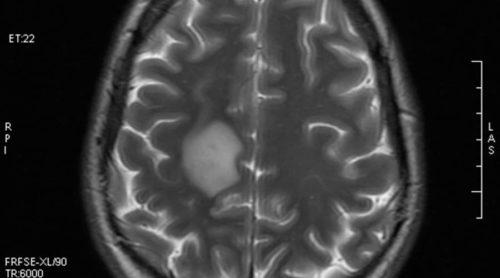

Диагностику заболевания осуществляют с помощью магнитно-резонансной томографии. При этом обнаруживаются множественные очаги демиелинизации. Преимущественно их обнаруживают в белом веществе головного мозга. Одновременно сосуществуют свежие и старые бляшки. Это является признаком постоянного процесса, объясняет прогрессирующий характер патологии.

Основной метод обнаружения очагов демиелинизации головного мозга – магнитно-резонансная томография. Она позволяет составить точную картину болезни. Введение контрастного вещества четче их очерчивает, позволяя выделить новые поражения белого вещества головного мозга.